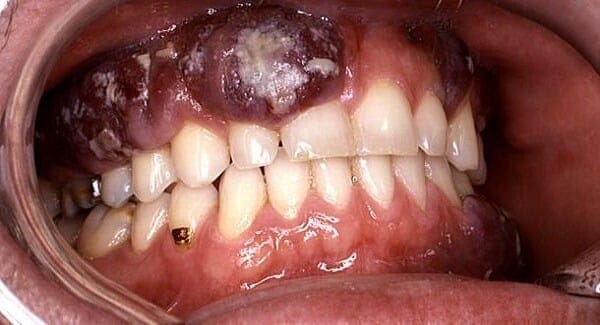

• Les premiers stades du cancer de la bouche peuvent provoquer une décoloration des tissus buccaux, des plaies et des ulcères buccaux qui ne guérissent pas, ainsi qu’un gonflement ou des bosses dans la bouche.